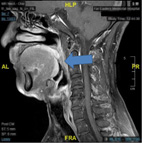

你知道嗎?其實志明除了有打呼症以外,他其實也有阻塞性睡眠呼吸中止症。打呼症的患者睡眠時,軟顎後區、舌根後區以及咽部的側壁與後壁等部位,因過多的脂肪沉積、睡眠時咽部肌肉放鬆或著是結構性問題(如:短下巴、短脖子或下巴內縮等),造成呼吸道部分塌陷而變得狹窄,限制了氣體的流量與氣流的通暢,為了經過比較狹窄的部位,氣流會加速,軟組織就會快速震動,進而發出聲響,形成鼾聲,並且在吸氣時更為明顯。而所謂的阻塞性呼吸中止症則是打呼症患者若上述提到的呼吸道塌陷得更為厲害導致呼吸暫停或著是氣流量進出減少(如:圖一),導致睡著時血中含氧濃度下降的次數過多則稱為阻塞性呼吸中止症。

圖一、磁振造影顯示治療前病患口咽部出現明顯的呼吸道塌陷現象(箭頭處)